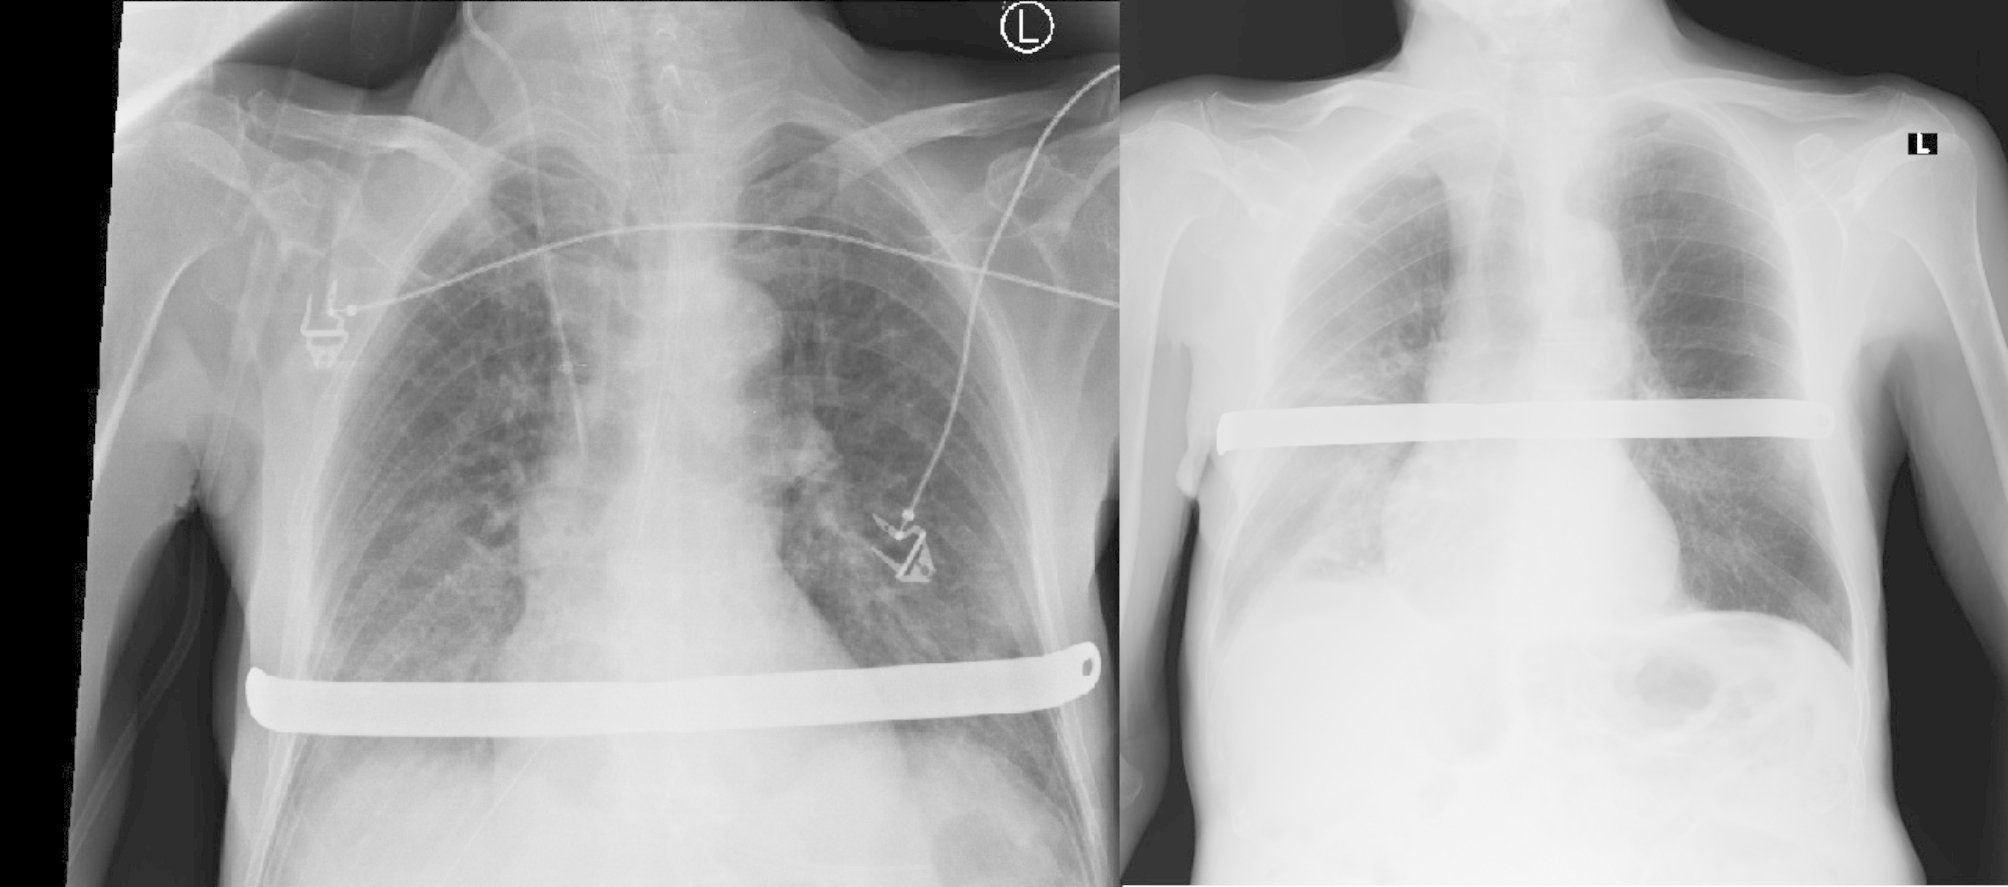

Next day, the chest tube was removed. Control x-ray of the chest showed reexpantion of lung parenchyma, no signs of fluid collection, correct position of the NUSS bar, stabilized fractures of chest bones. Patient did not need additional oxygen therapy.

Fig. 2.

X-ray day after surgery and day of discharge